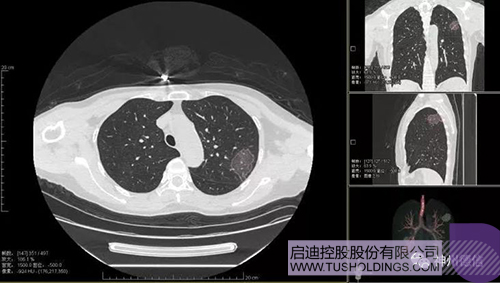

神州德信新冠肺炎檢測及智能量化分析系統(tǒng)

啟迪戰(zhàn)略投資企業(yè)神州德信作為國內(nèi)領(lǐng)先的肺部影像人工智能企業(yè),針對新型冠狀病毒肺炎開發(fā)了智能檢測及量化分析系統(tǒng),并在陜西、重慶等地定點醫(yī)院投入使用。該系統(tǒng)在疑似病例大規(guī)模快速篩查及精準診斷方面發(fā)揮了重要作用,特別是其具有的肺炎患者臨床影像跟蹤量化隨訪功能,為快速有效阻斷疫情擴散提供了有力武器。